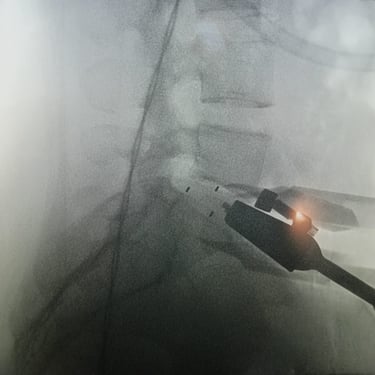

La cirugía ALIF (Anterior Lumbar Interbody Fusion), o Fusión Lumbar Intercorporal Anterior, es una técnica quirúrgica utilizada para tratar patologías de la columna lumbar como la degeneración discal, la inestabilidad vertebral o las hernias lumbares recurrentes. Mediante un abordaje anterior, se extrae el disco dañado y se coloca un injerto o caja intersomática que permite lograr la fusión estable entre las vértebras. Este procedimiento favorece una mejor restauración del espacio discal, alineación lumbar y preservación muscular. La cirugía ALIF es realizada por un equipo especializado en neurocirugía de columna, garantizando precisión y resultados funcionales óptimos.